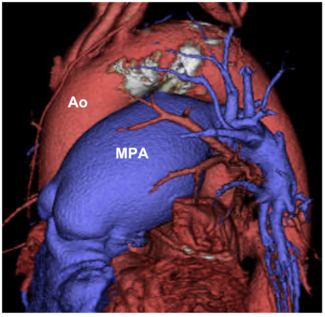

An 89-year-old woman was referred for closure of a patent ductus arteriosus (PDA). Contrast-computed tomography showed Krichenko type C PDA with severe calcification.